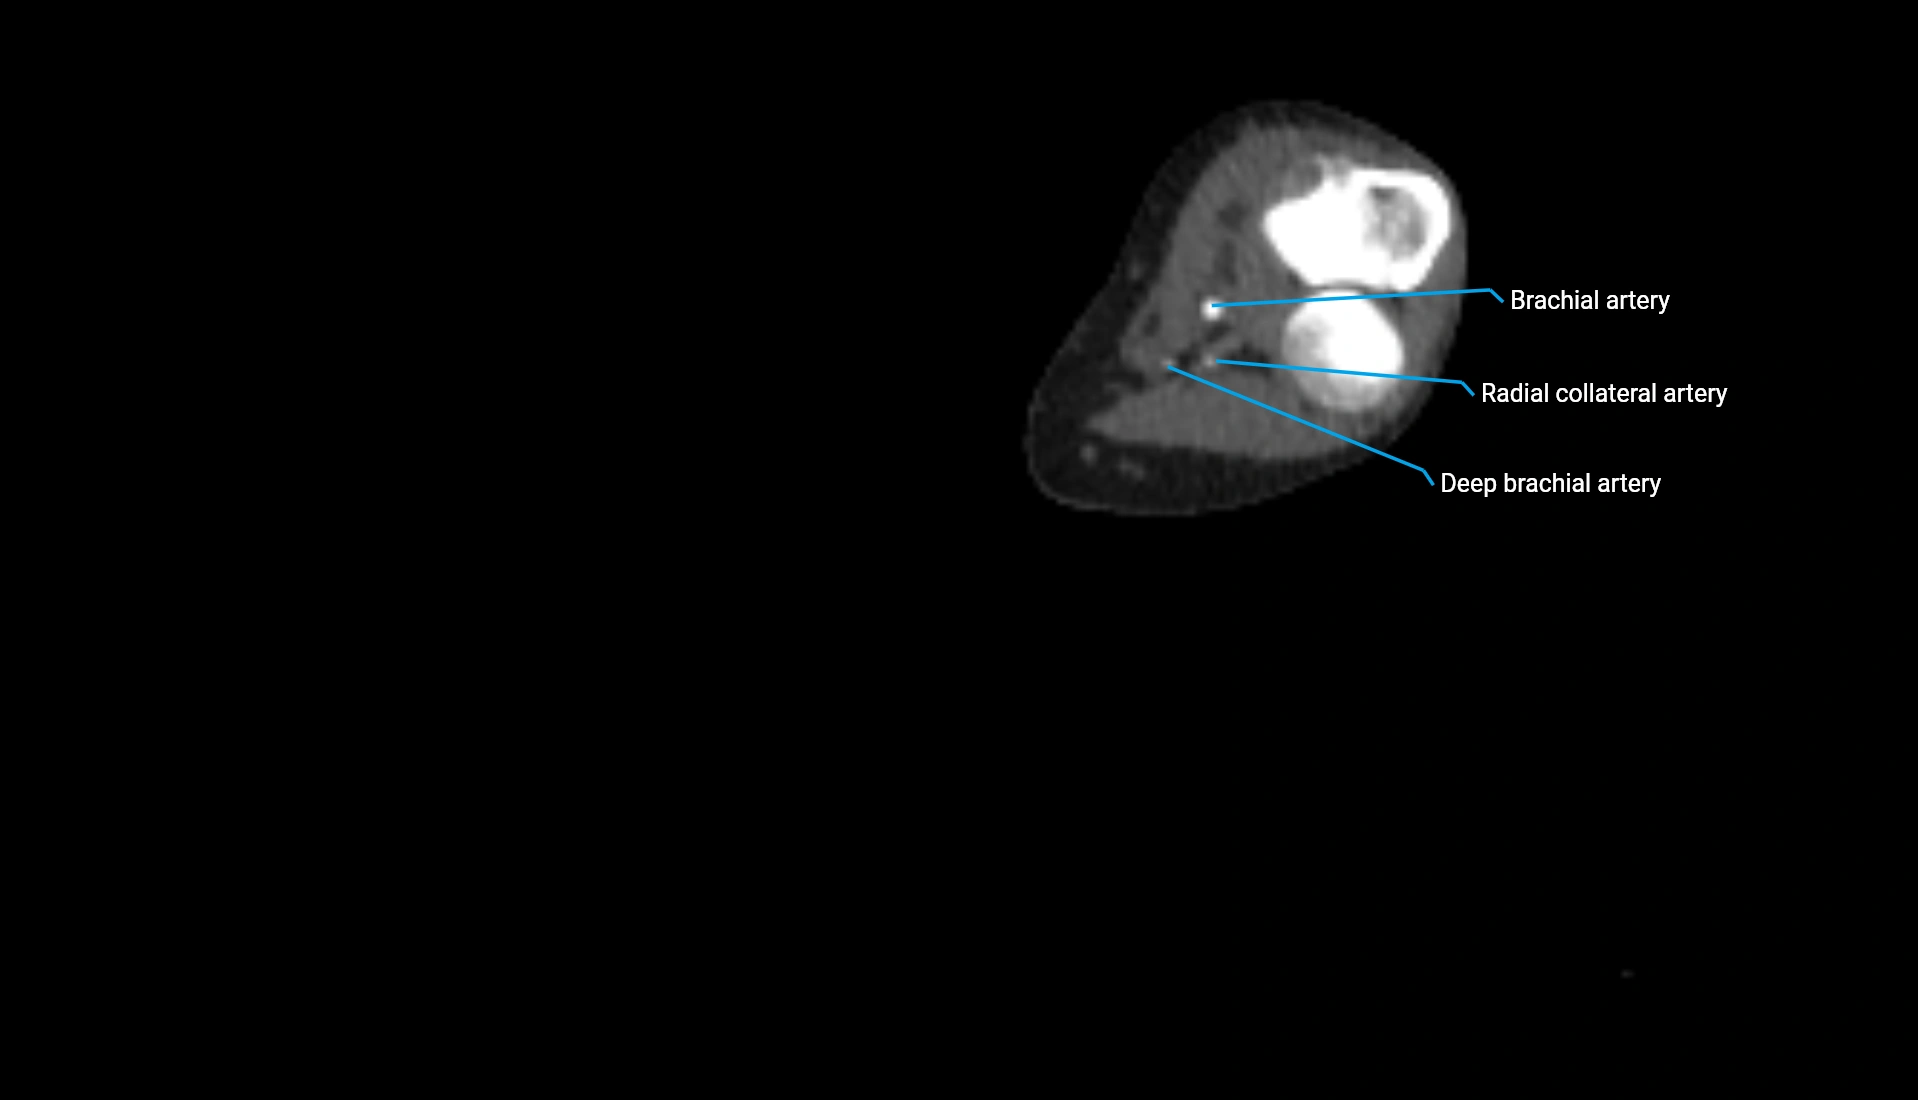

CT Appearance

Non-Contrast CT:

• Cortex: High-density, sharply defined

• Subchondral bone: Dense cancellous matrix

• Articular surface: Smooth concave contour articulating with the capitellum

• Excellent for evaluating bone integrity, alignment, and subtle fractures

Post-Contrast CT:

• Bone: No enhancement

• Joint capsule and synovium: Mild enhancement outlining the joint

• Improves contrast between soft tissues and bony margins

• Useful in detecting subtle joint abnormalities or postoperative changes